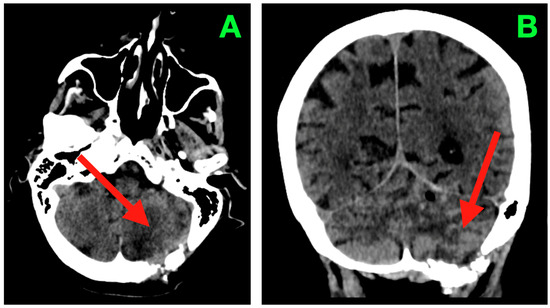

Advanced neuroimaging approaches are being used as valuable additional tools in characterizing brain lesions alongside conventional imaging techniques. The importance of advanced neuroimaging approaches is that they can provide information regarding the underlying pathophysiology of various brain lesions. Currently, both computed tomography (CT) and magnetic resonance imaging (MRI) include modern neuroimaging techniques, like dual-energy CT, photon-counting CT, perfusion MRI, functional MRI, diffusion-weighted MRI, diffusion tensor imaging, MRI spectroscopy, and MRI fingerprinting. Advanced approaches like radiomics analysis applied to CT and MRI images are increasingly being used for brain lesion characterization. Combining advanced neuroimaging approaches along with artificial intelligence techniques such as machine learning and deep learning algorithms will further promote and accelerate the adaptation of advanced neuroimaging methods in routine clinical neuroimaging. This Special Issue, entitled "Brain/Neuroimaging 2025", will include the application of advanced neuroimaging approaches for the characterization of brain lesions (tumors, demyelinating changes, ischemic stroke, hemorrhage, and infectious lesions) and neurodegenerative disorders, as well as the monitoring of treatment-induced brain lesions.